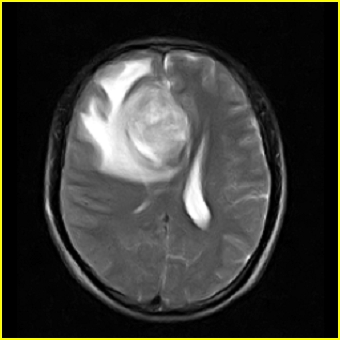

男,45岁,头部剧烈疼痛伴呕吐5天。

右侧额叶见较大的类圆形长t1信号环绕等t1环影,长t2信号环绕短等t2环,周围见明显水肿占位征,中线结构左移,男,45岁,头部剧烈疼痛伴呕吐5天。

右侧额叶,见一占位病灶,t1像病灶、水肿长t1;其间为短t1环行信号。t2像病灶、水肿长t2,其间为短t2环行信号。占位效应明显,中线左移,右测脑室受压闭塞。结合患者发病较急。首先考虑:右侧额叶脑脓肿形成。鉴别:1、转移瘤,多发多见2、胶质瘤。建议增强

t1加权肿瘤呈低信号,肿瘤壁呈等信号.t2 加权时肿瘤呈高信号,肿瘤壁呈等信号.

考虑1脑脓肿.2恶性胶质瘤.